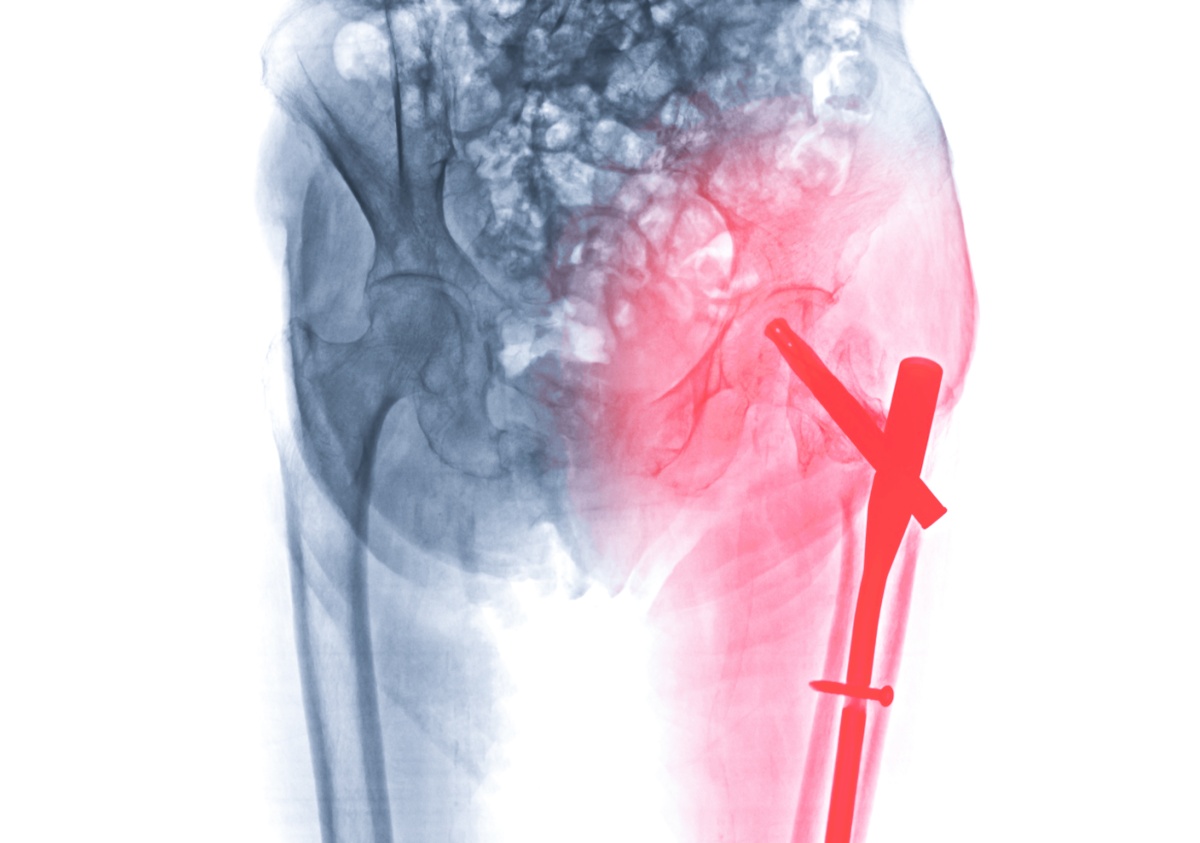

Periprosthetic fracture: Bone fracture around or near the hip implant from trauma or stress, requiring complex revision hip surgery with fracture management.

Expert Bone Loss Management in Revision Hip Surgery

Bone deficiency management is a major challenge in revision hip replacement surgery at Shivaan Hospital. Dr. Krunal Donda uses Paprosky classification and other systems to determine the optimal reconstruction strategy for each patient requiring complex revision hip surgery in Surat.

Treatment options include morselized bone grafting for contained defects where impacted bone chips provide structural support, structural allografts for segmental deficiencies, trabecular metal augments and cones for large acetabular defects, and custom triflange cups for severe pelvic discontinuity. Dr. Donda's expertise in bone reconstruction for revision hip replacement ensures optimal outcomes even in the most challenging cases.